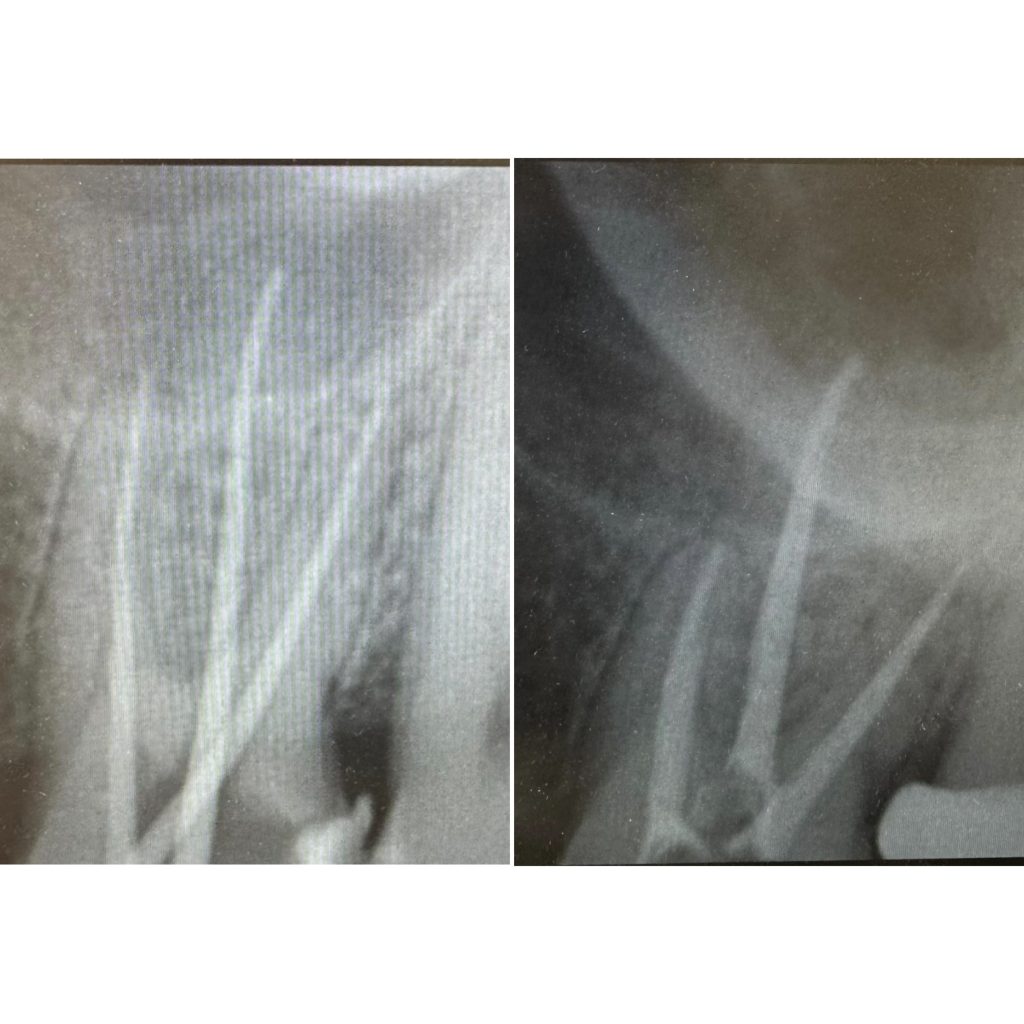

• Эндодонтическое лечение корневых каналов с использованием стоматологического микроскопа

2022 год – «Первичная эндодонтия с использованием современных клинических протоколов» Андрей Кольба

2023 год – «Первичная эндодонтия» Виталий Весна

2025 год – «Современные протоколы лечения эндодонтических пациентов» Dental Education Clinic,курс Елены

Драган